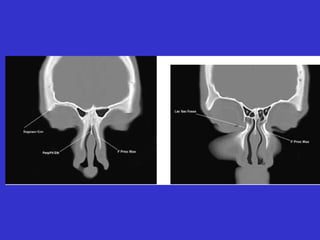

Este documento describe las diferentes proyecciones radiográficas utilizadas para examinar los senos paranasales, incluyendo las proyecciones básicas de Caldwell, Waters lateral y las proyecciones especiales como Hirtz y Waters mentonasal. También describe las diferentes estructuras anatómicas que componen el complejo ostiomeatal anterior y posterior de los senos paranasales.